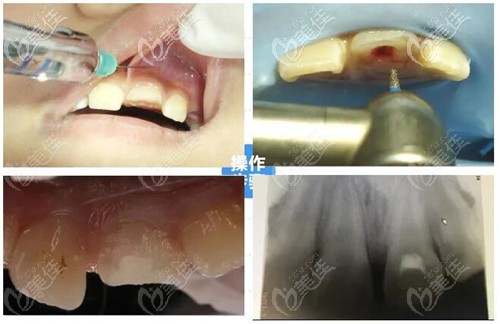

活髓切斷術(shù)是在局部麻木的方式下將牙冠部位的牙髓切斷并且去除,再用蓋髓劑覆蓋在牙髓斷裂上,以此來保留健康的牙齒根髓。

根管治療的方式和目的主要是清理牙齒根管內(nèi)的牙髓炎癥和壞死物質(zhì),通過適當(dāng)消毒充填根管達(dá)到牙髓的治療的效果,但主要是戰(zhàn)隊牙髓壞死不能保留活髓的情況下進(jìn)行治療。

活髓切斷術(shù)和根管治療都是牙髓病的治療,兩者的價格相差不大,我覺得樓主如果牙齒摔斷得先判斷牙髓是否活髓,如果活髓進(jìn)行活髓切斷術(shù)治療,然后再用進(jìn)行牙齒折斷處的修補。如果牙髓壞死那就先進(jìn)行根管治療,然后再考慮做種植牙或烤瓷牙修復(fù)。

親,做根管治療還是活髓切斷術(shù)得看你的牙髓情況。如果只是門牙折斷但是牙髓健康,修復(fù)辦法是活髓切斷術(shù)+斷冠再接術(shù),對牙齒折斷的部位保留健康牙髓,這樣牙髓健康,牙齒才能更好地維持,手術(shù)價格一般在500元起。

如果牙髓感染、病變就做根管治療,對牙齒炎癥消除,治療費用一般是300元起,一般需要2-4次治療才能完成。我覺得這兩個無論哪一個你得看醫(yī)生技術(shù),手術(shù)技術(shù)好兩項都效果都不錯,你參考下我的建議。